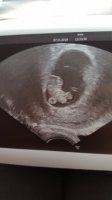

Å, så godt å høre! Gratulerer!Det gikk fint! Vi fikk se et lite bankende hjerte! Legen viste ikke grunnen til blødningene jeg har hatt.

ble flyttet fra 7+1 til 7+5, det forklarer de tidlig positive testene mine. Nå føles alt mer virkelig og. Lykke! ♡Da var jeg ferdig på ultralyd og fikk se en liten bamsemums med et hjerte som slårble flyttet fra 7+1 til 7+5, det forklarer de tidlig positive testene mine. Nå føles alt mer virkelig og. Lykke! ♡

Da var jeg ferdig på ultralyd og fikk se en liten bamsemums med et hjerte som slårble flyttet fra 7+1 til 7+5, det forklarer de tidlig positive testene mine. Nå føles alt mer virkelig og. Lykke! ♡

Fikk se en som dansa og bevegde armer og ben❤Den lille tilsvarte noen dager frem fra 8+5 til 9+1. Men fikk beskjed om å bruke menstermin foreløpig![]()